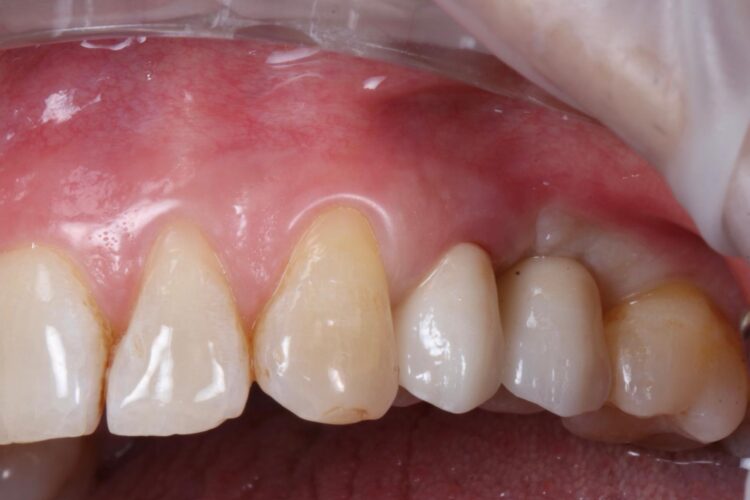

The implant in the UL5 was uncovered 3 months later to reveal healthy tissues. Three weeks later the final scan was taken (using trios intra-oral scanner) for the fabrication of the definitive crowns. On the day of crown fits both abutments were removed and the crowns seated. Due to the UL4 site having a custom healing abutment, which had been supporting our ideal emergence profile, it was much easier to engage this restoration and seat within the already moulded soft tissues.

With regards to the UL5 there was some blanching around the buccal aspect of the crown due to the use of a generic abutment, which does not offer any resemblance to the ideal emergence profile for the final restoration. Regardless good prosthetic positioning had been achieved to allow for screw-retained restorations in both implants. The final restorations were fitted as single unit layered zirconia crowns on titanium bases. The patient was delighted with the results.

Upon reflection of this case, a custom healing abutment may have delivered better soft tissue contouring than the generic abutment on the UL5. Healing may have taken longer, but it would have been easily tolerated by the patient and may have resulted in a better biological result with optimised aesthetics.